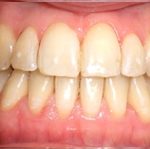

Avant traitement

Après traitement